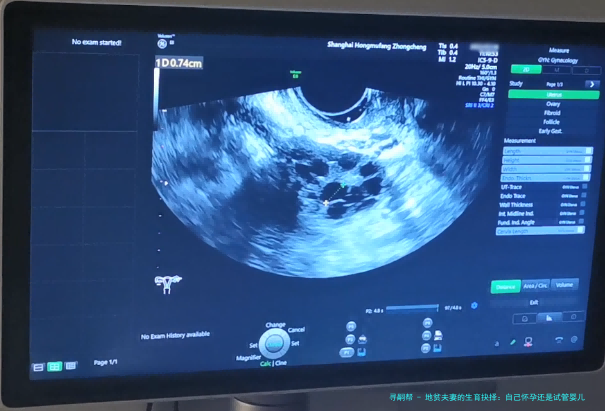

接下来,咱们聊聊试管婴儿技术。试管婴儿,学名叫体外受精-胚胎移植,特别是其中的PGD(植入前遗传学诊断)技术,简直就是地贫夫妻的救星。简单来说,医生可以在实验室里对胚胎进行基因筛查,只选择没有地贫基因的健康胚胎移植到子宫里。这样,就能大大降低孩子患病的风险。在我看来,这就像是为生育之路装上了“导航系统”,让你避开那些遗传陷阱。举个例子,前面提到的小张和小李后来选择了试管婴儿,通过PGD筛查,他们成功生下了健康的宝宝,现在家庭生活美满。不过,试管婴儿也有它的缺点,比如费用较高,过程可能比较繁琐,而且成功率不是100%。但总的来说,对于高风险的地贫夫妻,它提供了一个更安全的选项。